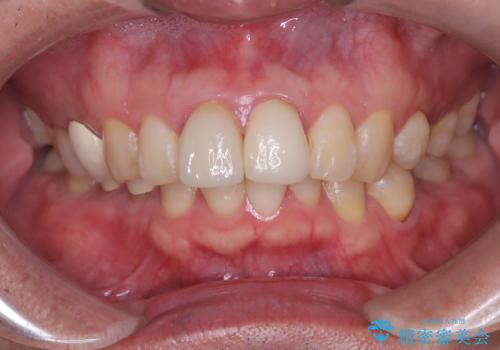

前歯の根のところに違和感がある|根尖性歯周炎|精密根管治療|オールセラミッククラウン|見た目も改善

- 前歯の違和感を主訴にご来院された患者様です。

根尖性歯周炎に罹患し根の先に膿が溜まっているのが原因でした。

精密根管治療後、オールセラミッククラウンで治療を行いました。

治療後、違和感は無くなりました。

治療後、違和感が無くなり、被せ物で歯の長さが揃い見た目も改善されとてもご満足していただけました。